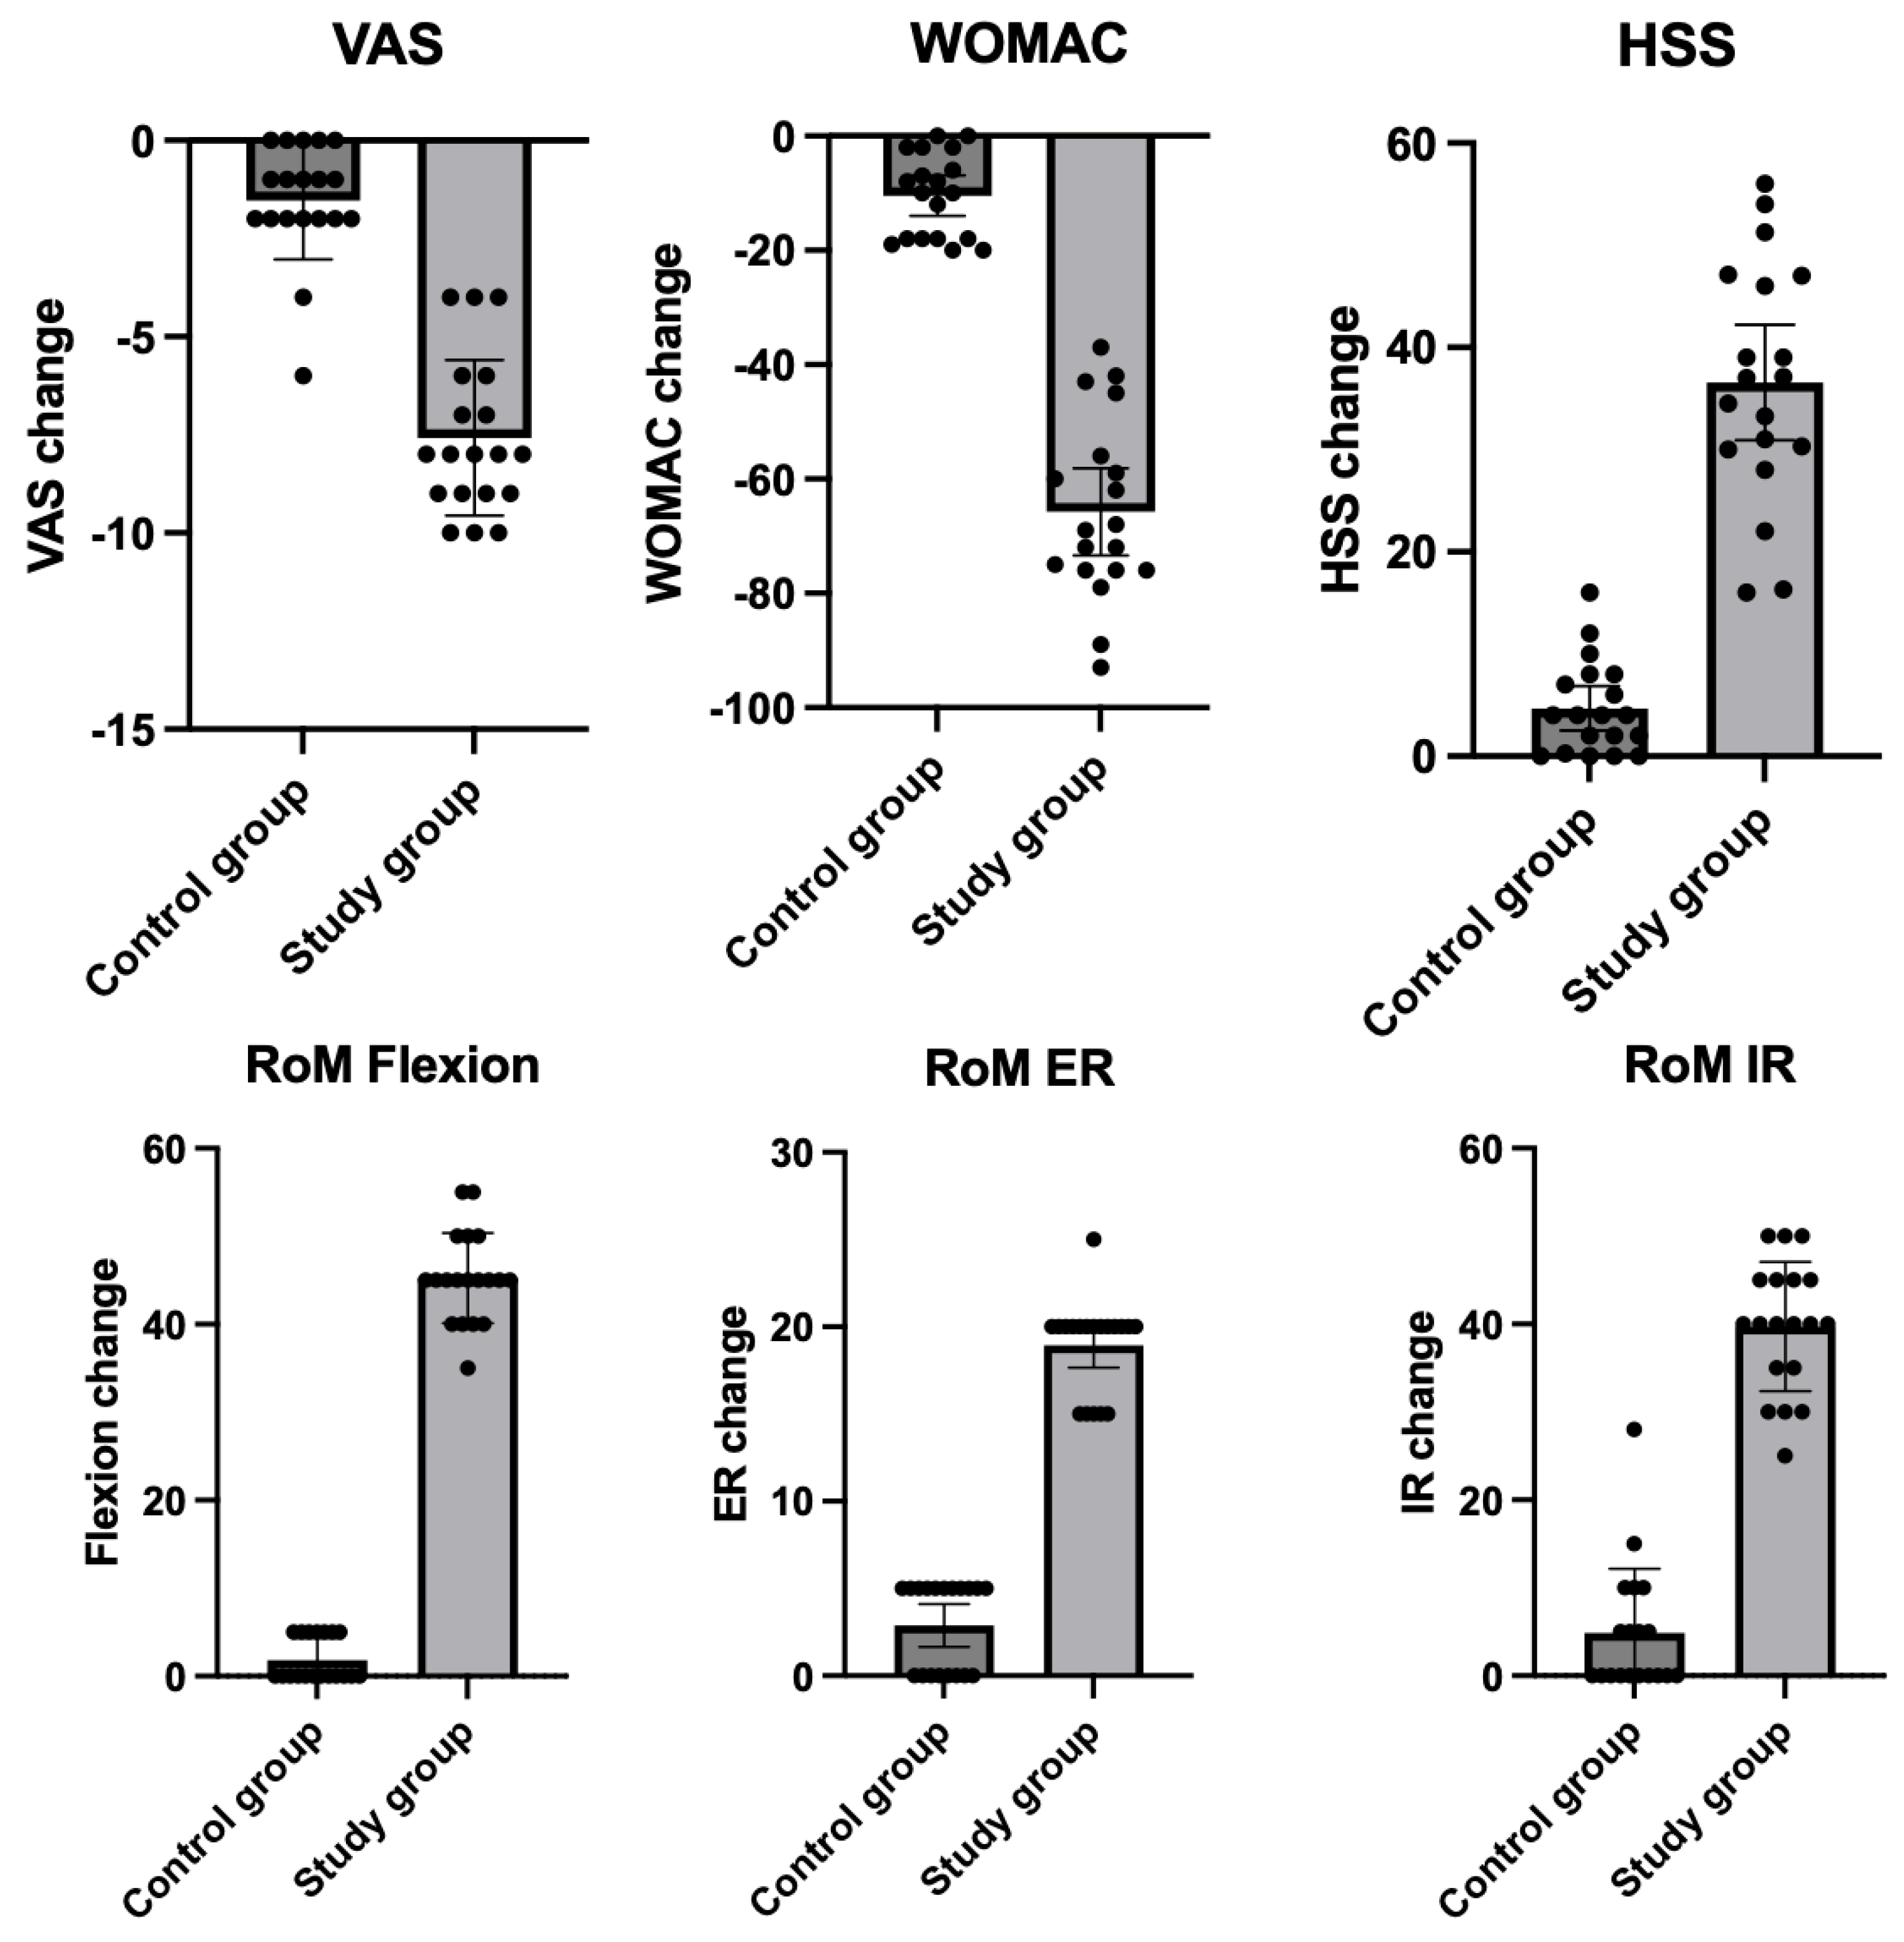

| Study Group (N = 19) | Control Group (N = 19) | p | ||||

| Variable | Mean | 95% CI | Mean | 95% CI | ||

| VAS | At baseline | 7.8 | 6.9–8.6 | 8.8 | 8.3–9.3 | 0.09 |

| After treatment | 0.2 | 0.0–0.4 | 7.3 | 6.3–8.2 | <0.001 | |

| Change | −7.6 | −8.5–−6.6 | −1.5 | −2.2–−0.8 | <0.001 | |

| p for change | <0.001 | 0.004 | ||||

| WOMAC | At baseline | 76.2 | 71.1–81.3 | 88.7 | 85.1–92.3 | 0.0002 |

| After treatment | 10.5 | 5.1–15.9 | 78.3 | 73.2–83.4 | <0.001 | |

| Change | −65.7 | −73.3–−58.1 | −10.4 | −19.9–−6.9 | <0.001 | |

| p for change | <0.001 | <0.001 | ||||

| HSS | At baseline | 56.4 | 51.3–61.5 | 48.7 | 42.4–55.0 | 0.052 |

| After treatment | 93.0 | 90.5–95.5 | 53.4 | 47.5–59.3 | <0.0001 | |

| Change | 36.6 | 30.9–42.2 | 4.7 | 2.5–6.8 | <0.0001 | |

| p for change | <0.001 | 0.004 | ||||

| RoM flexion | At baseline | 94.0 | 91.6–96.3 | 90.8 | 87.8–93.8 | 0.09 |

| After treatment | 139.2 | 136.6–141.8 | 92.63 | 90.2–95.1 | <0.001 | |

| Change | 45.3 | 42.8–47.7 | 1.84 | 0.6–3.0 | <0.001 | |

| p for change | <0.001 | 0.24 | ||||

| RoM ER | At baseline | 9.7 | 8.4–10.6 | 8.7 | 7.6–9.7 | 0.29 |

| After treatment | 28.4 | 27.0–29.8 | 11.6 | 10.4–12.7 | <0.001 | |

| Change | 18.7 | 17.7–20.2 | 2.9 | 1.7–4.1 | <0.001 | |

| p for change | <0.001 | 0.012 | ||||

| RoM IR | At baseline | 21.6 | 18.7–24.5 | 21.7 | 19.0–24.4 | 0.95 |

| After treatment | 61.3 | 57.3–65.3 | 26.6 | 24.5–28.7 | <0.001 | |

| Change | 39.7 | 36.2–43.3 | 4.9 | 1.4–8.4 | <0.001 | |

| p for change | <0.001 | 0.048 | ||||